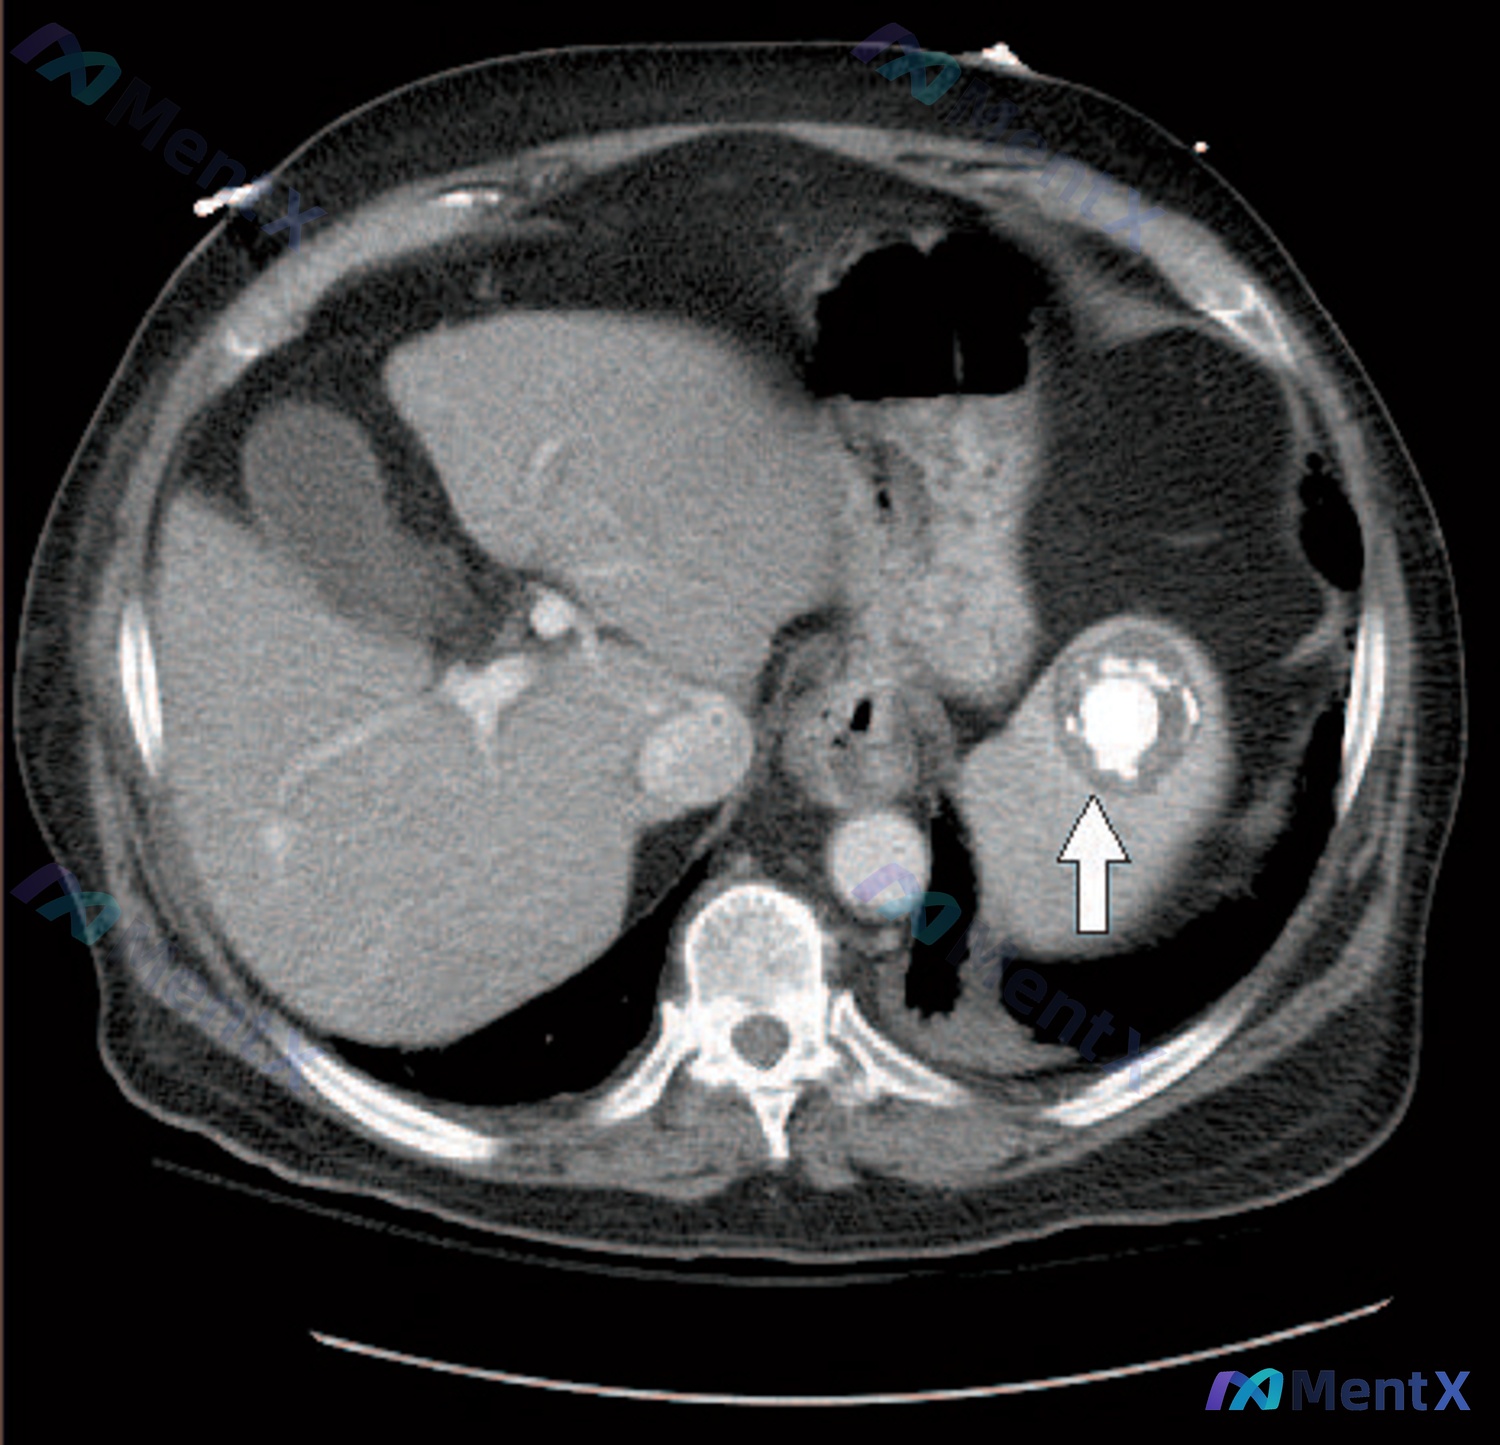

这张CT平扫的核心异常非常明确,在脾脏实质中部:

- 典型形态:病灶核心是极高密度的钙化影(亮白色),周边绕了一圈低密度区,最外层是很明显的环形/「蛋壳样」钙化壁;

- 边界:病灶和周围正常脾实质分界比较清楚;

- 其他背景:肝脏、胰腺、胆囊、双肾、腹腔大血管、腹腔间隙这些都没看到明显急性异常,没有积液、积气,也没有明确的肿大或渗出。